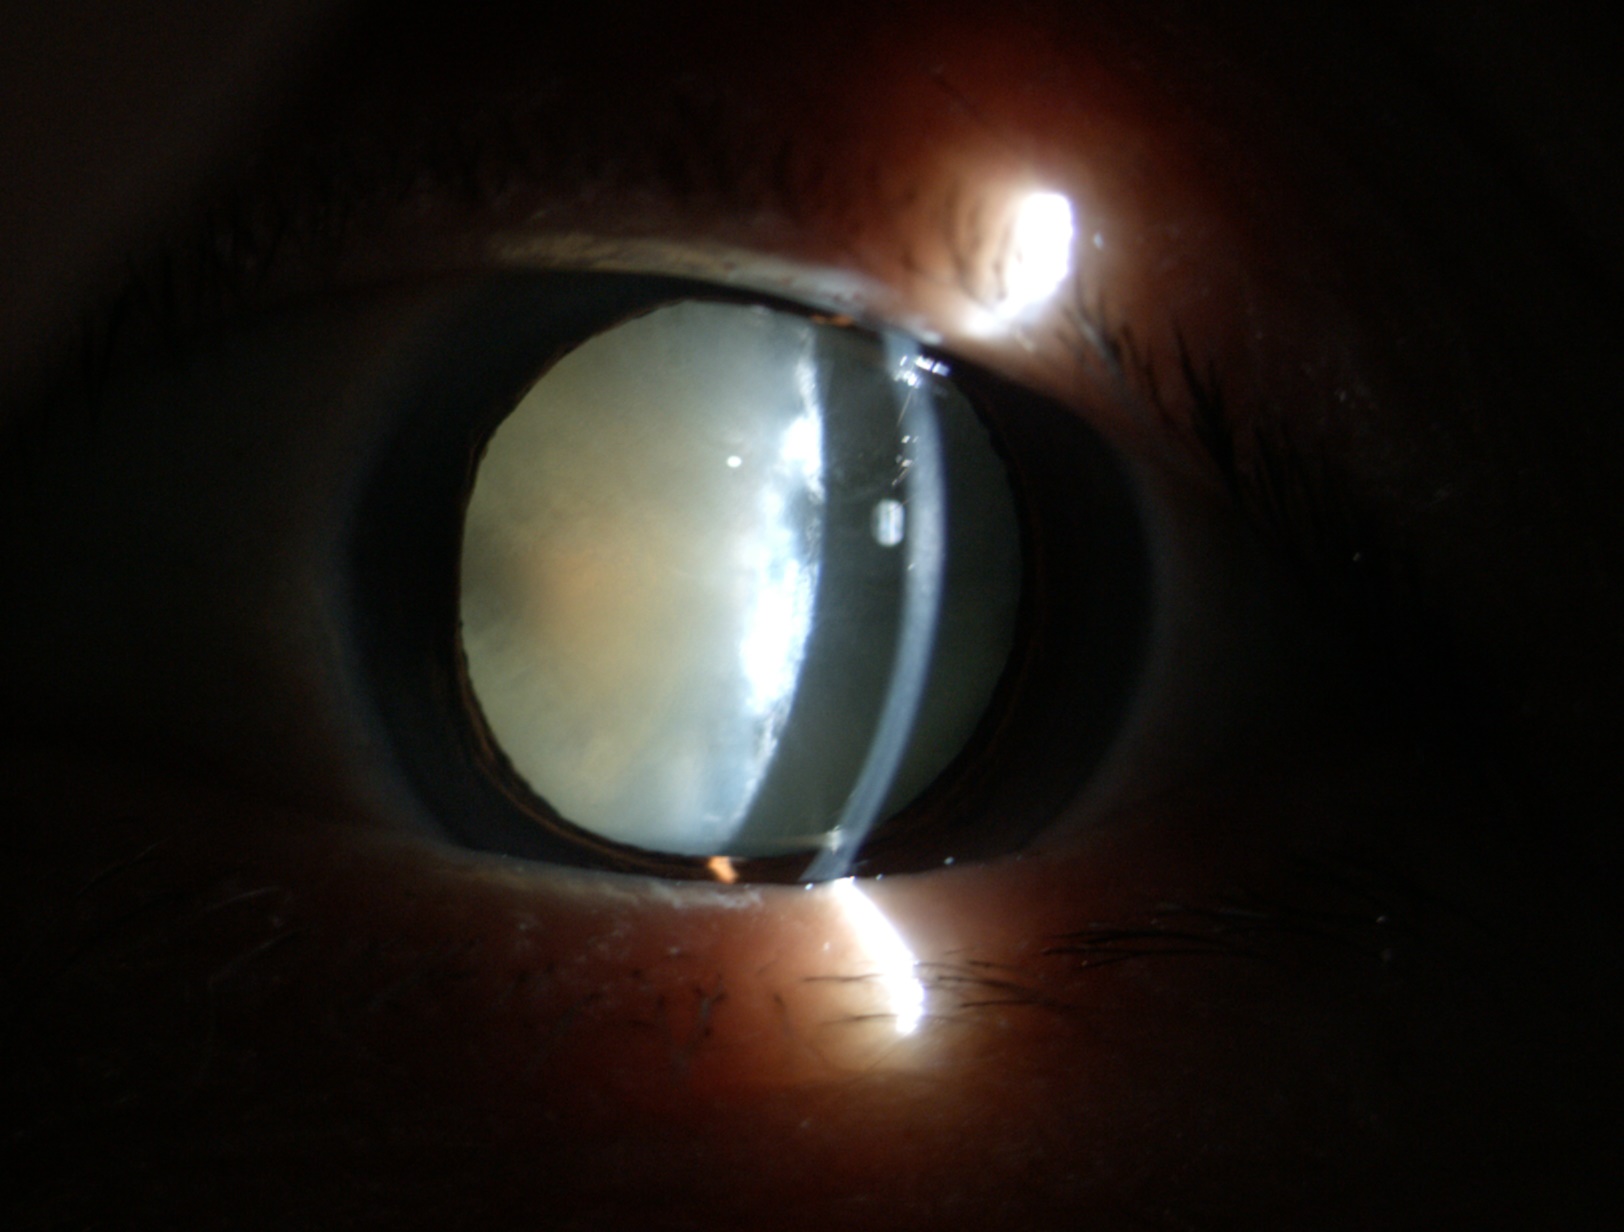

老年性白內(nèi)障

夏季強烈的陽光通常使瞳孔變小,此時往往視力下降更明顯,適合手術(shù)者更應(yīng)當機立斷。